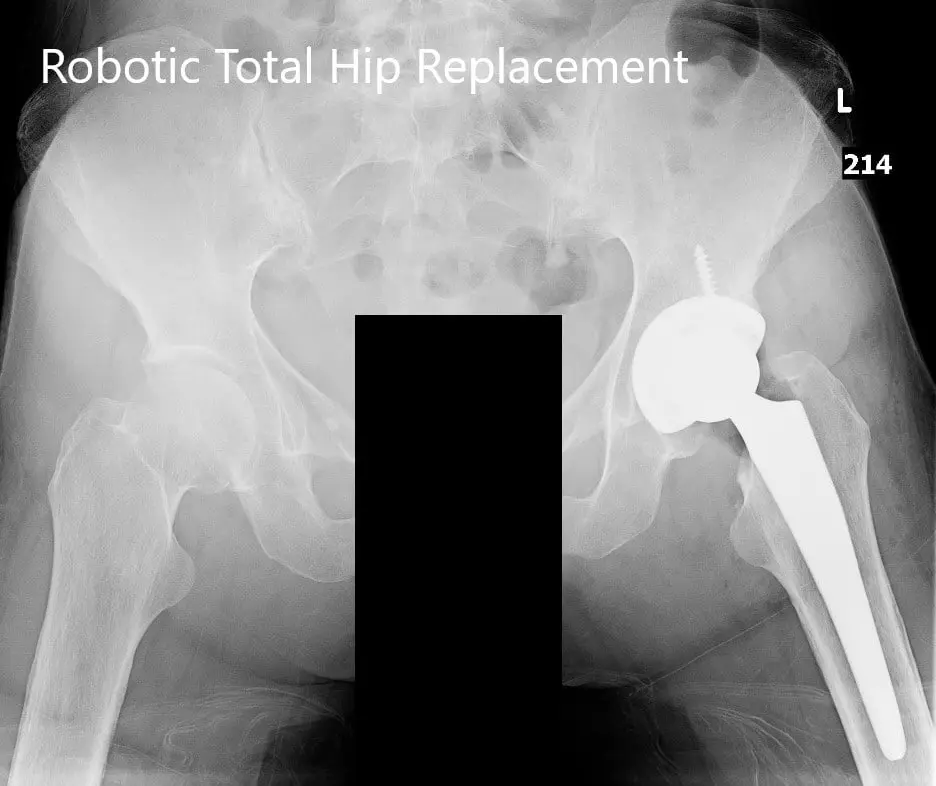

Postoperative X-ray of the pelvis with both hip joints in the AP view

Postoperative X-ray of the pelvis with both hip joints in the AP view.